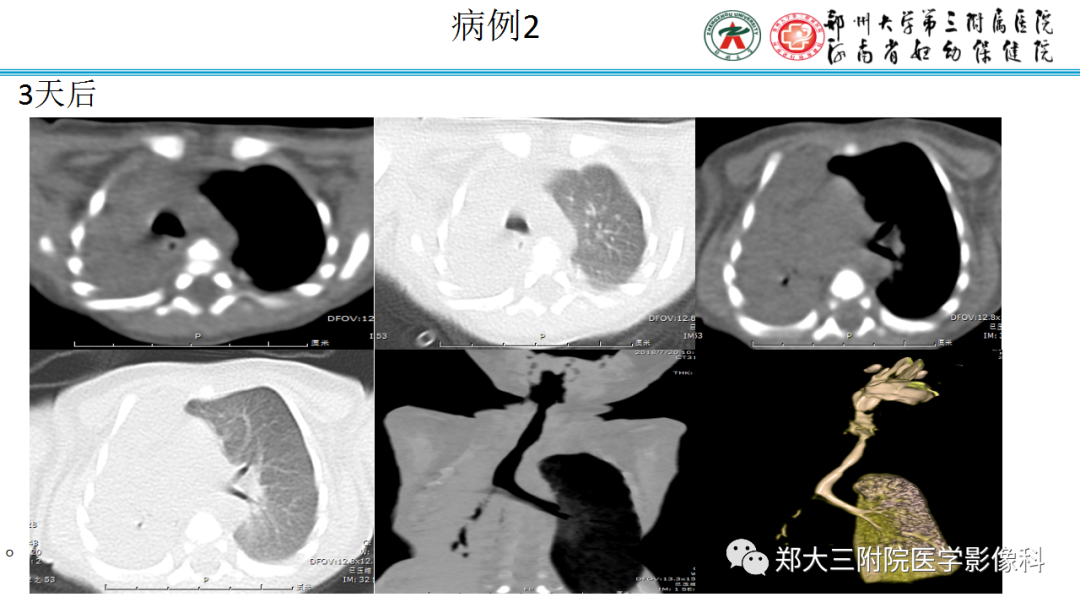

病例图片: